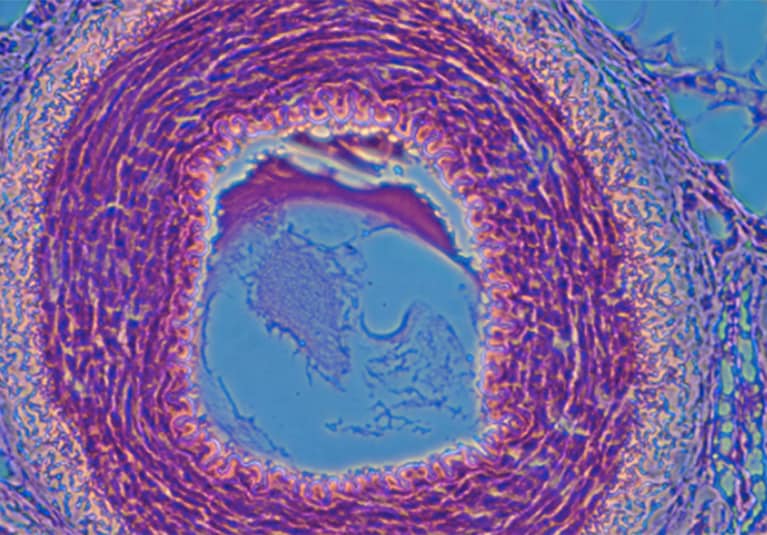

Diffuse alveolar hemorrhage (DAH) caused by capillaritis occurs in about 25 percent of patients with GPA and MPA, either at presentation or during a disease relapse, whereas DAH is extremely rare in EGPA. Patients with DAH usually have detectable ANCAs, either targeting proteinase 3 (PR3) or myeloperoxidase (MPO). Lung nodules, masses or cavities are disease-defining consequences of necrotizing granulomatous inflammation in GPA. Tracheobronchial involvement also is a feature predominantly of GPA, rarely found in MPA but not in EGPA. Asthma and eosinophilic pneumonia are disease-defining features of EGPA when they occur in patients with features of small vessel vasculitis.